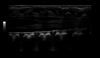

Accurate image quality and non-invasive imaging tools help you deliver fast, confident diagnoses across a wide range of patientsʼ conditions, from neonate cranial scans to abdominal or pelvic pain.

LOGIQ Ultrasound, with cSound™ Imageformer, enables delivering images of incredible uniformity from near to far field. Thereʼs no need to manually adjust the focus - the information you need is there, instantly.

B-Flow imaging - non-Doppler technique - enables direct, real-time visualization of blood flow echoes with no vessel wall overlap to obscure details